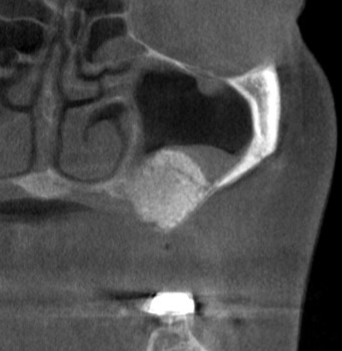

そこで、まず、2本目、3本目の部位に、サイナスリフトという上方の空洞に人工骨を填入する骨造成術を行いました(下の写真、3段目)。

後ろ2本の骨の高さは確保できましたので、インプラント埋入を行ないました。